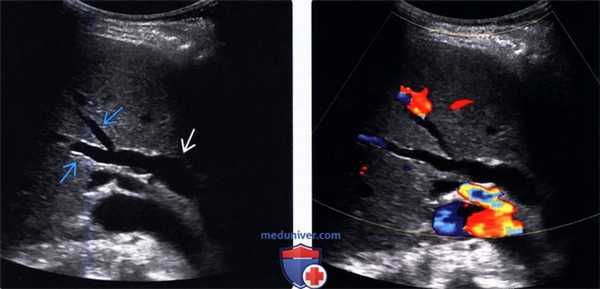

• УЗИ в черно-белом режиме

о Дилатация внутрипеченочных протоков

- Диаметр протоков > 2 мм

- Тубулярные анэхогенные ветвящиеся структуры, сопутствующие воротным венам:

Симптом «параллельного канала»

Зачастую самыми первыми из внутрипеченочных протоков расширяются протоки левой доли печени

- Расширенные протоки могут быть извитыми и иметь неравномерный просвет

- Проксимально у ворот печени сливающиеся тубулярные структуры формируют звездчатую структуру

о Дилатация внепеченочных протоков:

- Диаметр общего желчного протока > 6-7 мм или более чем 40% диаметра прилегающей воротной вены

- Анэхогенная тубулярная структура, в воротах печени параллельная основному стволу воротной вены и перпендикулярная печеночной артерии

- Расширение протоков может распространяться на внутрипеченочные протоки

• Цветовая допплерография:

о Позволяют достоверно дифференцировать расширенные протоки (в которых отсутствуют признаки кровотока) от прилегающих сосудистых ветвей печеночной артерии и воротной вены

(Левый) На косом трансабдоминальном УЗ срезе в печени определяется умеренное расширение общего желчного протока и ответвляющихся внутрипеченочных протоков; эти изменения вызваны обструкцией протоков опухолью головки поджелудочной железы (не показана).

(Правый) При цветовой допплерографии у того же пациента отмечается отсутствие кровотока в расширенных тубулярных структурах, что указывает на то, что это и в самом деле расширенные желчные протоки. Следует выполнять цветовую допплерографию в повседневной практике для подтверждения дилатации желчных протоков.